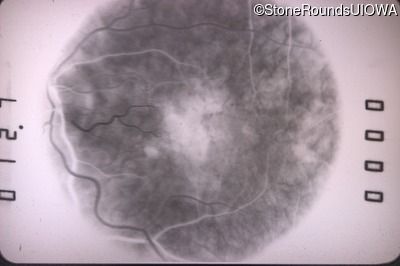

Fluorescein Angiography - Left - 20/160

Exemplar